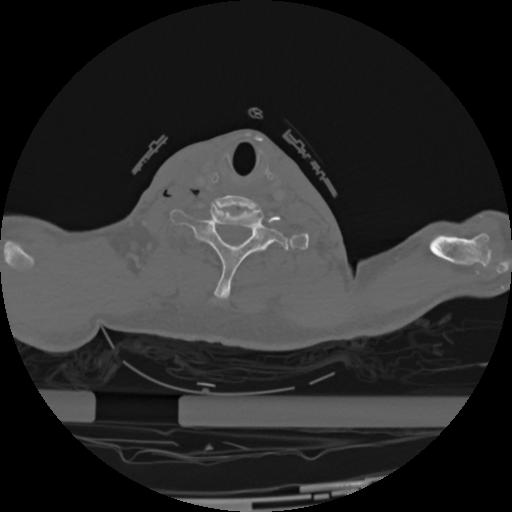

22 ANGIO,CE,Vol,0.5,ANGIO,,